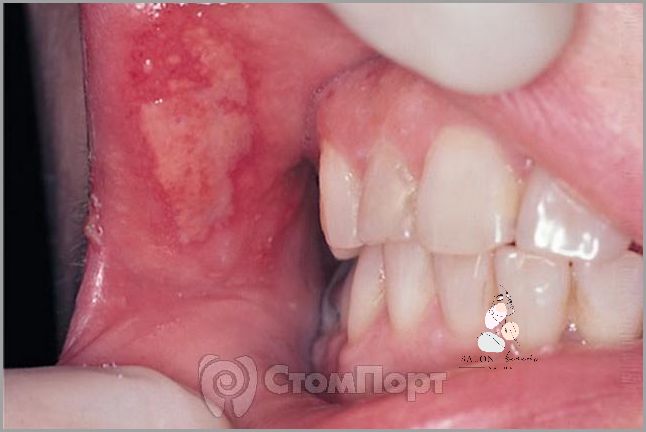

Zapalenie jamy ustnej to stosunkowo powszechna choroba, która dotyka ludzi w każdym wieku. Zwykle wywołuje je infekcja bakteryjna lub wirusowa, która wpływa na błony śluzowe jamy ustnej. Występowanie zapalenia jamy ustnej może być spowodowane przez niewłaściwe dbanie o higienę jamy ustnej, czynniki dziedziczne, infekcje wirusowe, zmiany hormonalne lub nadużywanie pewnych produktów. Objawy zapalenia jamy ustnej mogą się różnić, w zależności od rodzaju infekcji, ale najczęstsze z nich to ból i pieczenie w jamie ustnej, zaczerwienienie i obrzęk dziąseł, białe lub żółte plamki na języku lub błonach śluzowych, a także obecność krwi w ustach lub nieprzyjemny zapach.

Zapalenie jamy ustnej jest stanem zapalnym wywołanym przez szereg zarazków lub bakterii. Może być również wywołane przez alergeny lub inne czynniki drażniące. Objawy zapalenia jamy ustnej są bardzo charakterystyczne, obejmując ból i swędzenie, obrzęk i zaczerwienienie, a także tworzenie się pęcherzyków w jamie ustnej. W zależności od rodzaju zapalenia jamy ustnej, leczenie może obejmować zarówno leki przeciwbakteryjne, jak i leki przeciwhistaminowe.